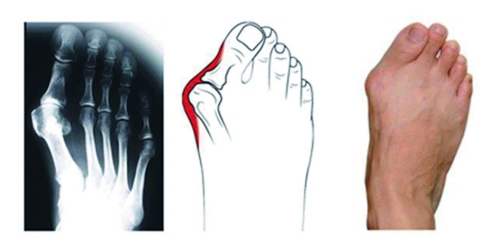

拇指外翻是一种足部畸形

据河南省中医院骨关节科主任医师王上增介绍,拇指外翻是指拇指向外偏斜移位超过正常生理角度的一种足部畸形,多见于成年女性,是目前最常见的足部疾病。拇指外翻常表现为拇囊炎,拇囊炎是关节内侧出现骨赘,也就是人们常说的骨刺。骨刺处的软组织与鞋子摩擦、挤压,导致皮肤红肿,出现积液。拇指外翻严重者甚至可以挤到第二、第三脚趾的下方,造成脚趾偏斜,甚至出现拇指关节脱位及骨性关节炎。